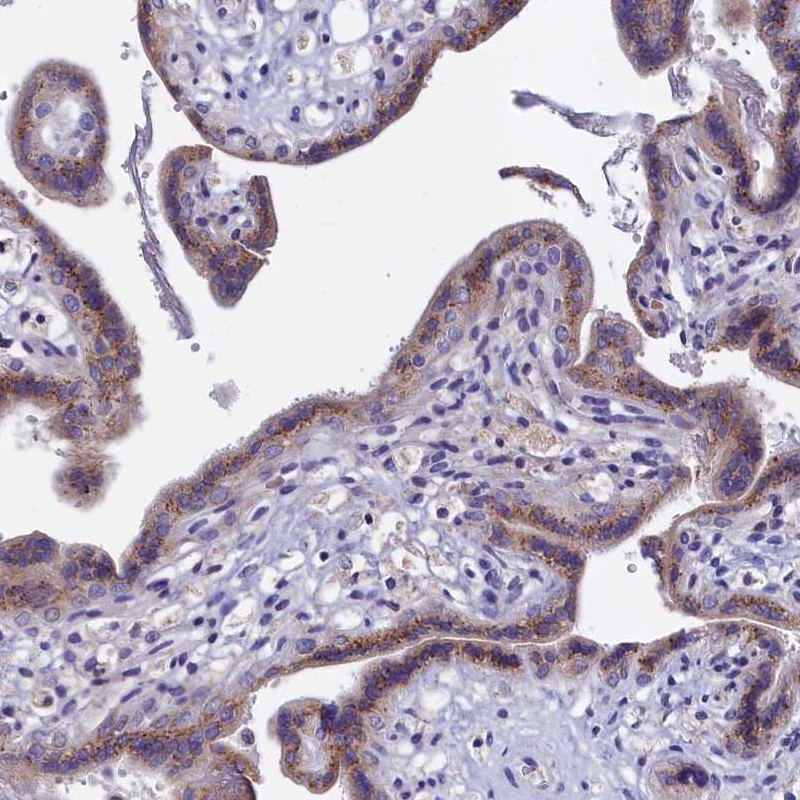

Immunohistochemical staining of human placenta shows cytoplasmic positivity in trophoblastic cells.